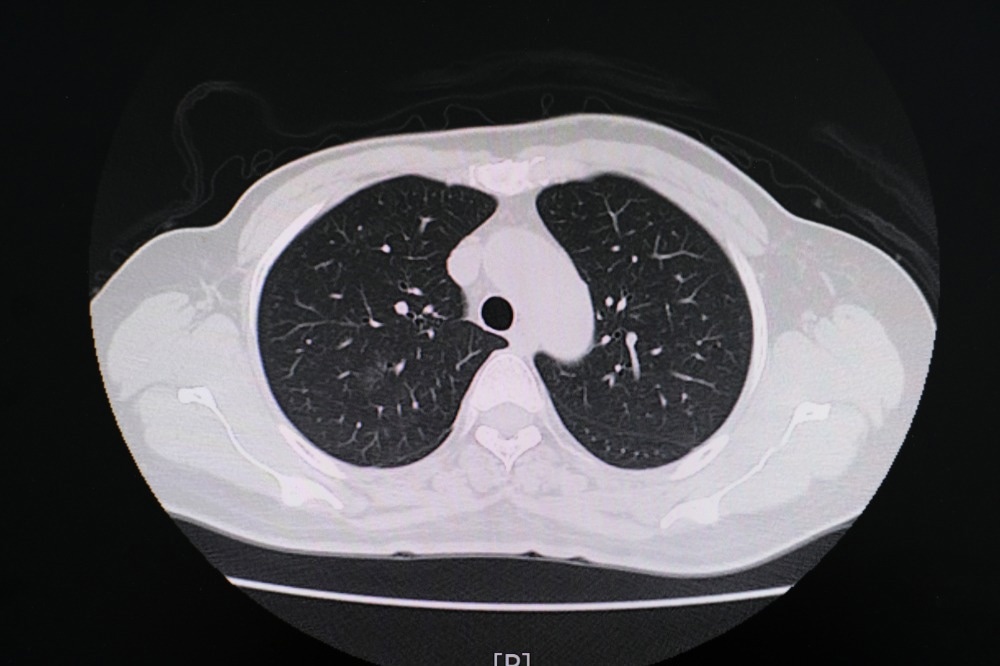

Study: Chest CT Findings in Marijuana Smokers. Image Credit: PIJITRA PHOMKHAM / Shutterstock.com

In a recent Radiology journal study, researchers report chest computed tomography (CT) findings that the lungs of marijuana smokers exhibit more significant levels of airway inflammatory markers and emphysema as compared to those of tobacco-only smokers.

In addition to pulmonary function tests, CT lung imaging can also provide important information on the impact of marijuana smoking on the lungs.

As compared to non-smokers, the CT findings for marijuana smokers indicated different rates of emphysema, bronchial thickening, bronchiectasis, mucoid impaction, and centrilobular nodules, all of which are CT markers for airway inflammation. Gynecomastia was also reported in 38% of marijuana patients as compared to 16% of non-smokers.

Upon comparison of CT findings between marijuana and tobacco-only smokers, the researchers reported differences in bronchial thickening, bronchiectasis, and mucoid impaction. Furthermore, higher rates of emphysema were observed in age-matched marijuana smokers as compared to tobacco-only smokers of 93% and 67%, respectively. No differences were observed when comparing the occurrence of centrilobular nodules between marijuana and tobacco-only smokers; however, this may be due to the high rate of tobacco smokers who also smoked marijuana.

Paraseptal emphysema was also more frequently identified in marijuana smokers as compared to the lungs of tobacco-only smokers. Conversely, centrilobular emphysema was primarily visualized in the lungs of tobacco-only smokers.